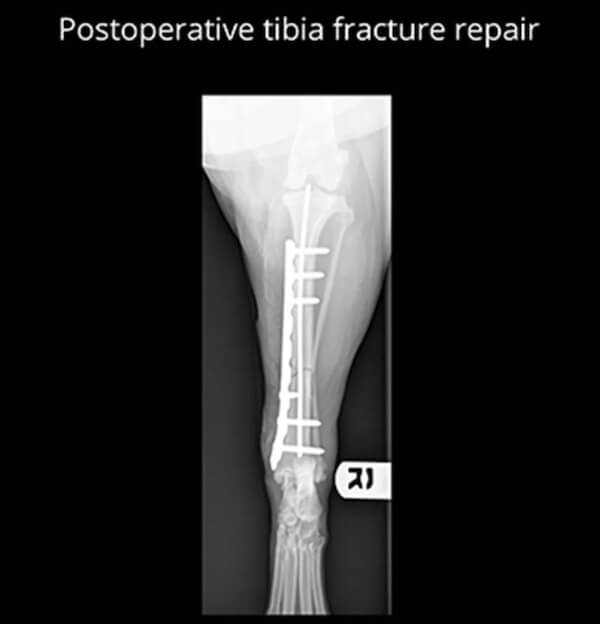

Each fracture is evaluated individually using digital imaging, and treatment plans are tailored to the type of fracture, the pet's age, size, activity level, and overall health. Surgical repair may involve pins, plates, screws, or other stabilization methods to promote proper healing.